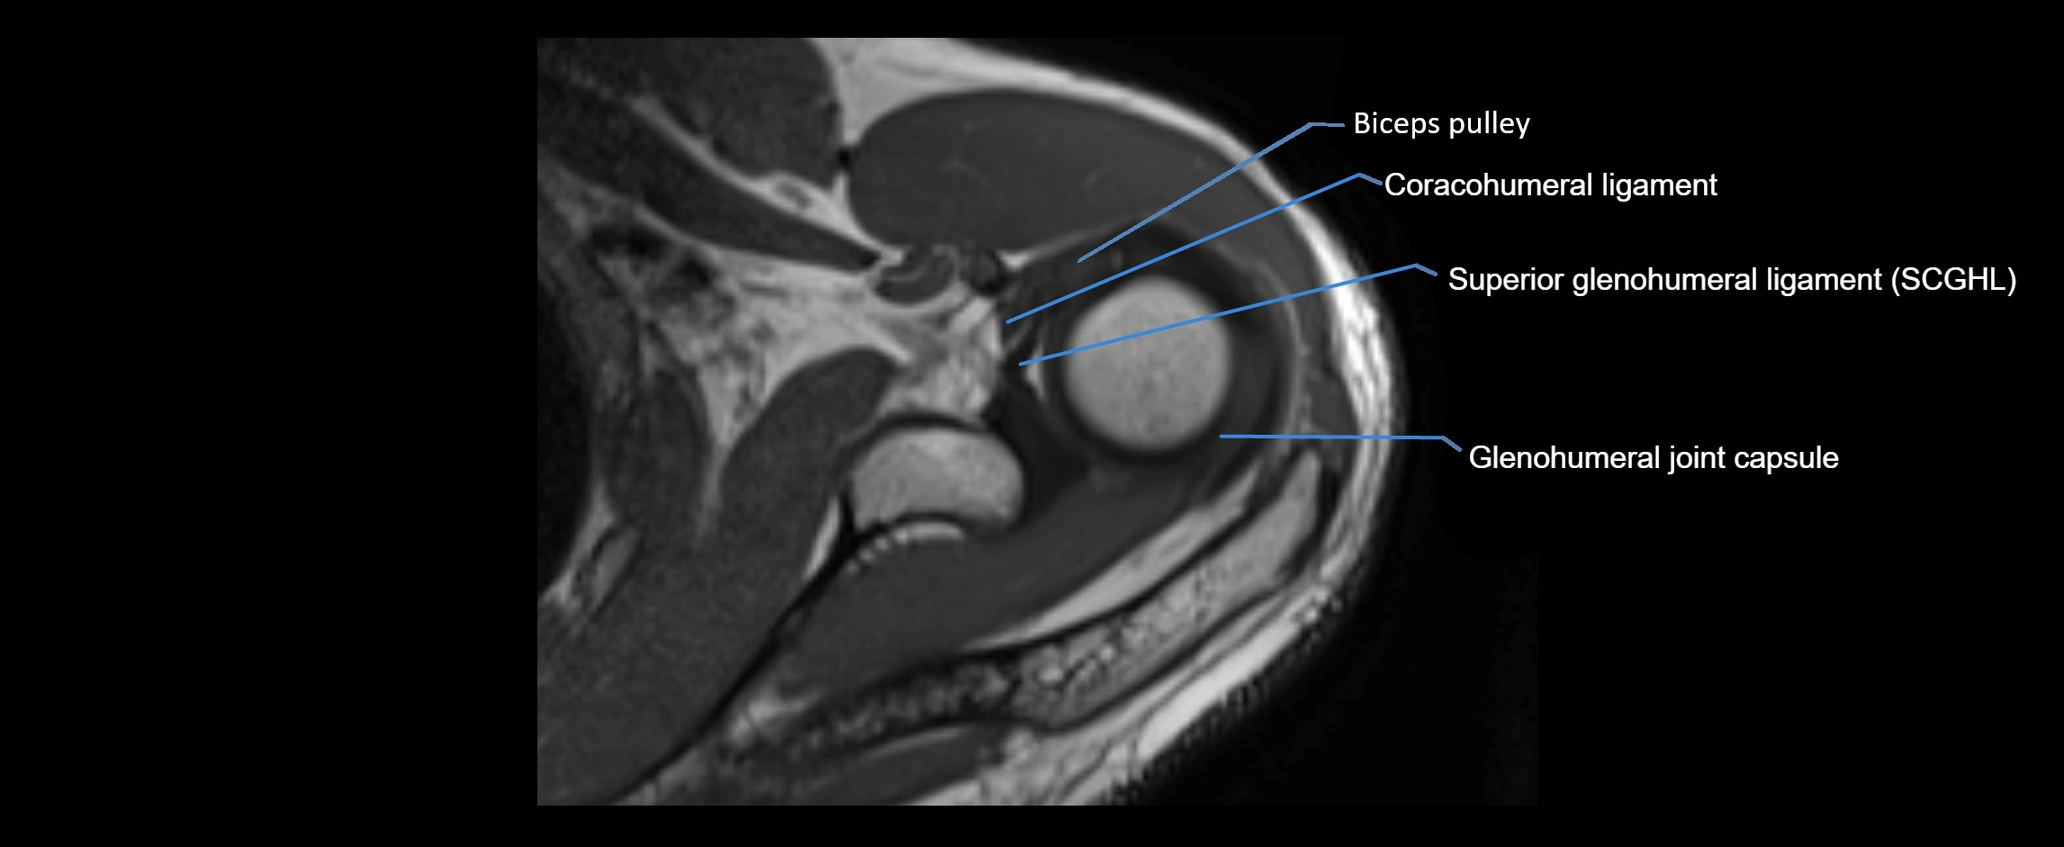

MRI images

image